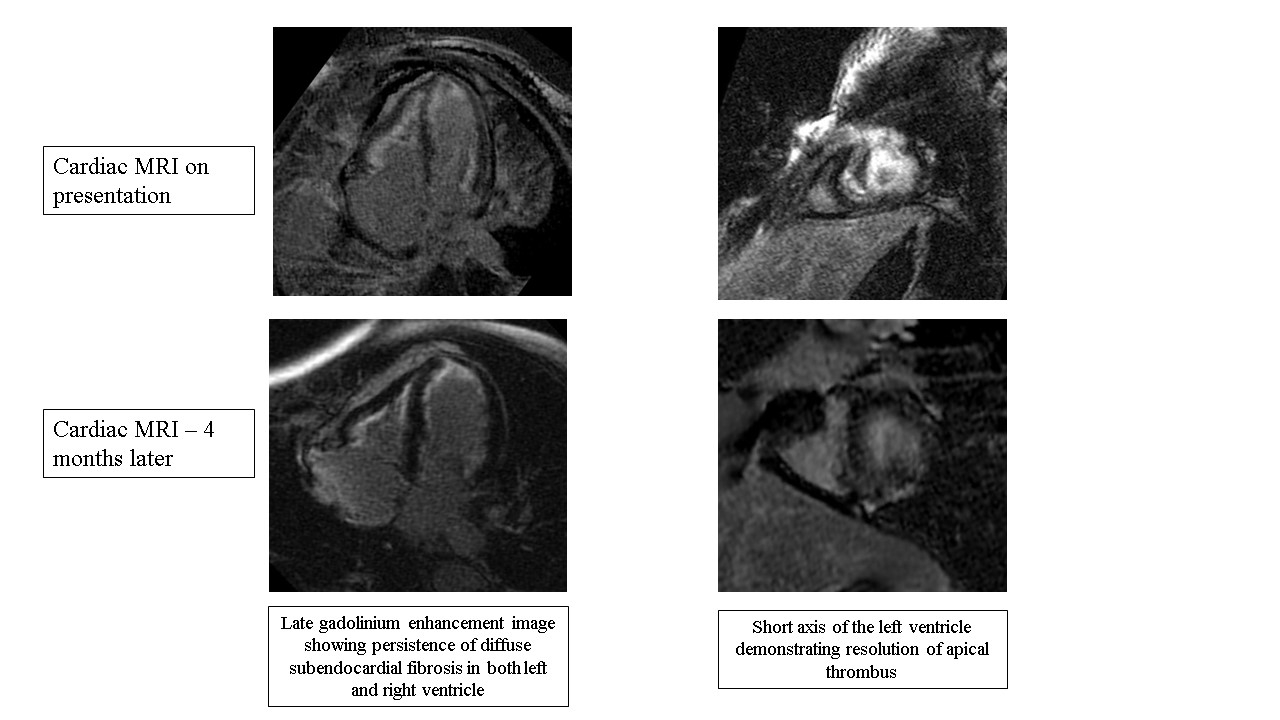

Physical exam was remarkable for signs of volume overload. Electrocardiogram showed sinus tachycardia and diffuse nonspecific T-wave inversions. Laboratory studies revealed a complete blood count significant for eosinophilia of 26,000, representing 79.5% of the differential. Troponins were negative. A brain natriuretic peptide was 903 pg/ml. Echocardiogram findings included mild reduction in biventricular systolic function with wall motion abnormality seen at the apex. Cardiac MRI (CMR) demonstrated mild biventricular systolic dysfunction, left ventricular intracavitary filling defect consistent with thrombi, and diffuse biventricular subendocardial late gadolinium enhancement (LGE) consistent with fibrosis. Abatacept was stopped with resolution of eosinophilia. Patient was treated with a short course of steroids and initiated on warfarin for left ventricular thrombi. Repeat CMR four months later showed resolution of left ventricular thrombi and biventricular dysfunction, with persistence of diffuse subendocardial fibrosis in both left and right ventricles.

CMR demonstrates findings consistent with Loeffler Endocarditis as evident by ventricular intracavitary filling defects and diffuse biventricular subendocardial late gadolinium enhancement. Initial management of involves prompt discontinuation of the suspected offending drug. Corticosteroids may be employed to mitigate eosinophilic infiltrate and myocardial inflammation. Diagnostic modalities such as cardiac imaging, endomyocardial biopsy, and laboratory testing play crucial roles in confirming the diagnosis and assessing severity. Follow-up CMR can help follow the response to cessation of the offending agent and rule-out confounding disease processes, as seen in this case. In conclusion, abatacept-induced eosinophilic endocarditis is a rare phenomenon that is poorly understood. Drug-induced eosinophilic endocarditis should be considered as a differential in patients that develop heart failure symptoms and eosinophilia after initiating abatacept.